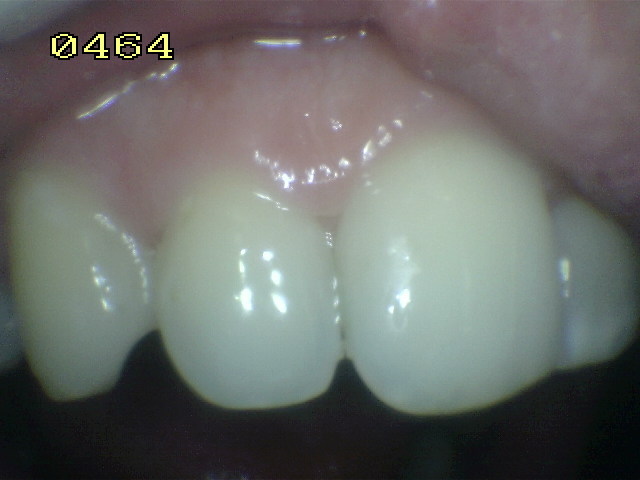

Una morfología de la fisura estrecha, con forma de botella de "Coca-Cola" genera un nicho ecológico ideal para la colonización de cualquier bacteria productora de ácidos. Al no poder remover en forma períodica dicho biofilm de una zona tan estrecha, el ataque ácido genera una lesión cariosa en la dentina, con un aspecto de esmalte intacto a la inspección visual, o sea un típico código 3 y 4 de ICDAS Completo. (Caries Moderada para el ICDAS COMBINADO)

Por este motivo es importante realizar el sellado de las fosas y fisuras de molares y premolares cuando comienza su erupción dentaria, como método de prevención eficaz de caries.

Código 3 (Caries moderada) in vitro. Los códigos 3 in vivo debe ser sellado para evitar el avance del proceso carioso. (MNO)